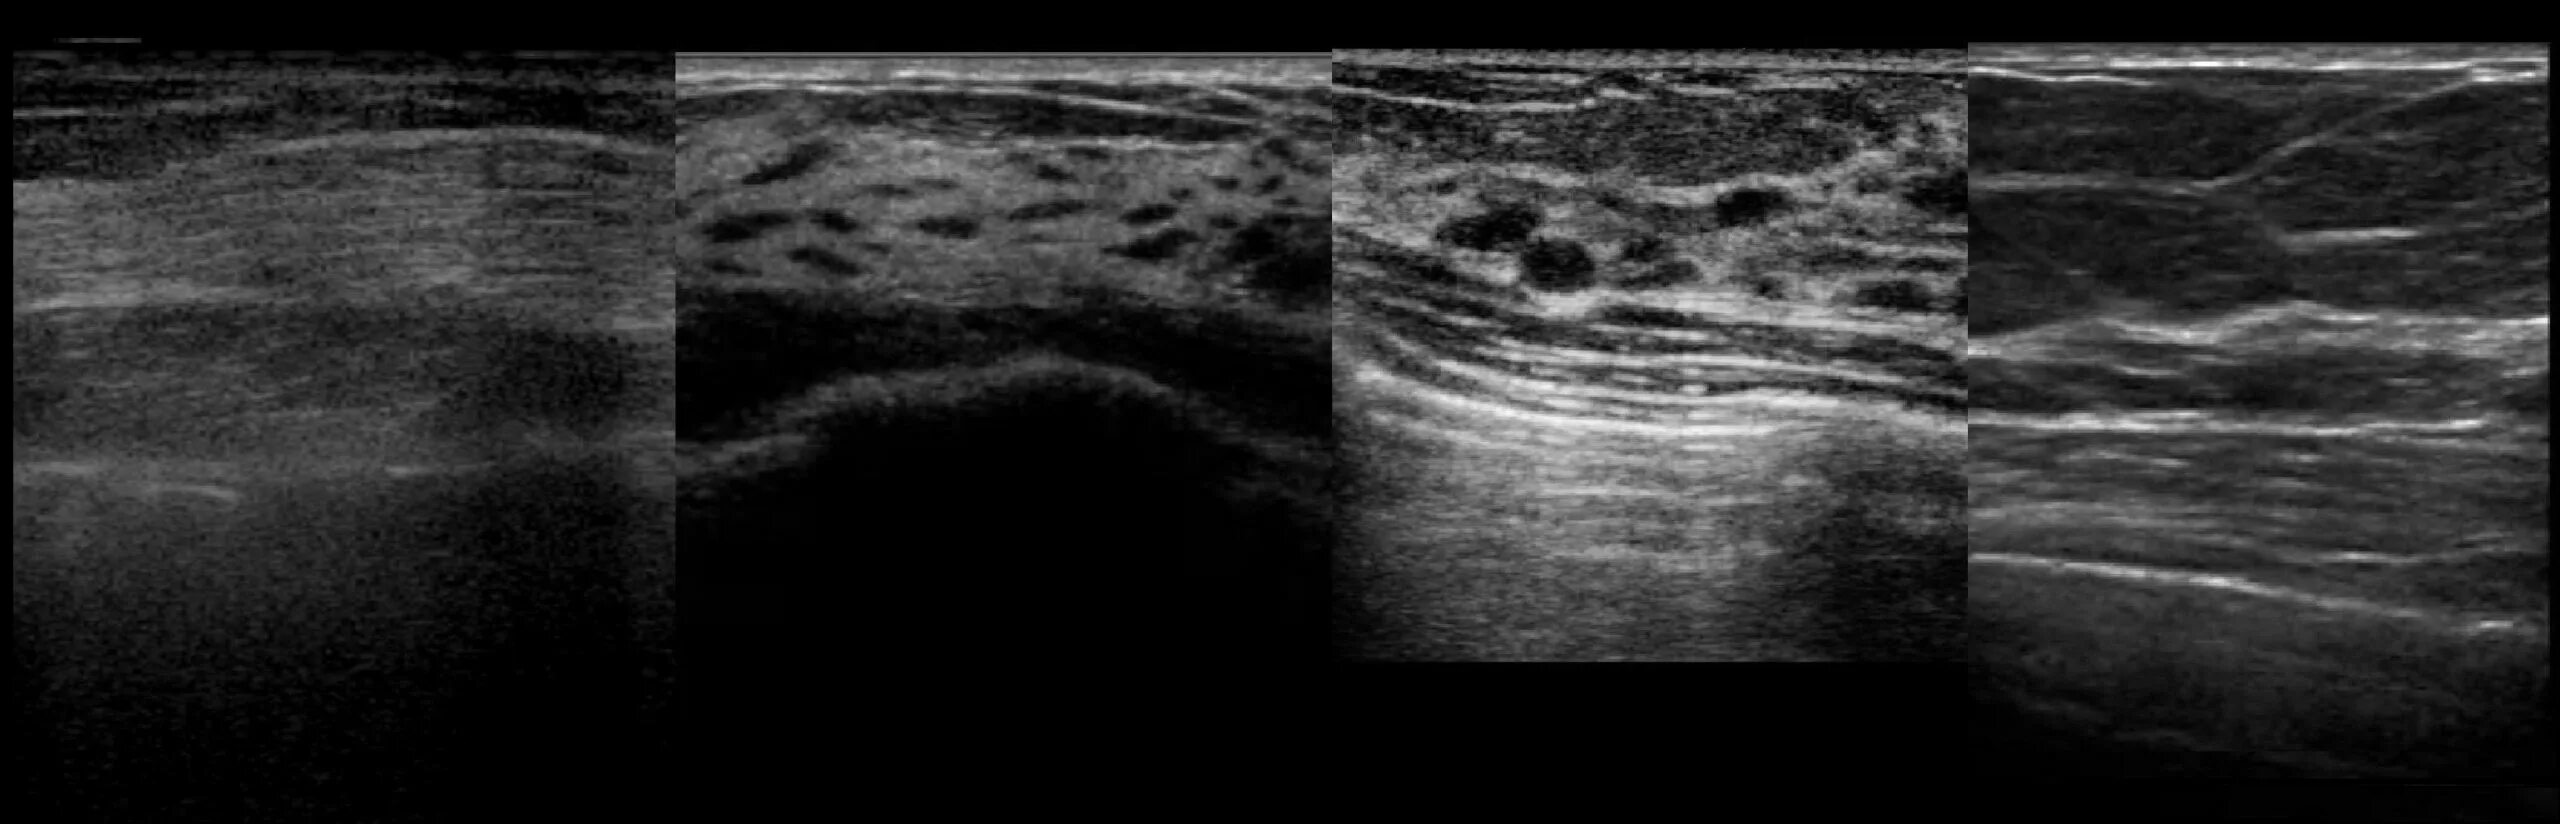

Расширен проток